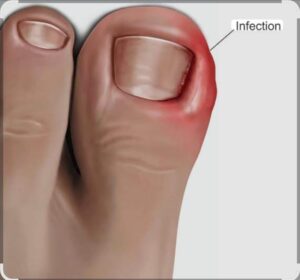

Read MoreNail removal surgery

Nail removal surgery, also known as nail avulsion, is a...

Read MoreHydrocele surgery